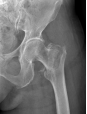

12月17日,贵州航天医院第88次晨读会由我院骨一科主任、副主任医师陈明勇作学术交流,他以“肱骨近端骨折并肩关节脱位的手术治疗”为题,全面讲解了该损伤的手术策略、术中血供保护理念及内侧支撑重建技术等内容,并通过多个典型病例图文资料分享了从损伤机制分析、手术步骤实施到术后随访评估的完整过程与关键细节,为临床处理此类复杂骨折提供了较为全面的技术参考,有助于在手术规划中结合个体情况开展针对性治疗。 贵州航天医院 骨科专家简介 陈明勇 骨一科主任,副主任医师 临床擅长:从事创伤骨科工作约20年,对骨缺损、骨不连、骨肿瘤、肢体畸形等的肢体矫形重建及功能重建,慢性化脓性骨髓炎的根治治疗、糖尿病足的保肢治疗、快速康复理念(ERAS)下的老年骨折的诊治,四肢复杂骨折的诊治,四肢骨折等微创手术治疗具有丰富的临床经验。 2004年毕业于遵义医学院临床专业,曾在中国人民解放军总医院、广西医科大学第一附属医院、上海第六人民医院骨科进修。中国中西医结合学会骨伤科专业委员会横向骨搬移治疗糖尿病足及微血管网再生学组首届委员,遵义市医学会创伤分会常务委员。 瞿 晖 骨科党支部书记,骨二科主任,副主任医师 临床擅长:对骨科的常见病、关节外科、脊柱外科及运动医学疾病的诊治具有丰富的临床经验,熟练掌握骨科手术操作技术。 毕业于遵义医学院临床医学系,2005年前往广州中山大学第一附院骨显微医学部进修学习,2011年前往成都华西医院进修学习,并多次在省内外学习骨科相关知识,是中华医学会骨科分会会员。 赵小锋 中共党员,骨二科副主任,副主任医师 临床擅长:从事骨科临床工作11年,对骨科常见病、多发病诊疗有较为丰富的临床经验,擅长脊柱相关疾病诊断及治疗,尤其是颈、腰、腿疼痛疾病诊断及治疗,擅长胸腰椎骨折微创经皮穿刺内固定术、经皮穿刺椎体成形术、经皮穿刺脊柱内镜下腰椎间盘摘除术、单纯开创腰椎间盘摘除术、腰椎滑脱复位椎间植骨椎融合内固定术、腰椎管狭窄减压融合内固定术及人工髋、膝关节置换术等。 2012年毕业于遵义医学院外科学专业硕士研究生,2019年参加“遵义市115医学人才精英计划”于上海交通大学第一附属医院培训学习,2023年于北京大学第三人民医院脊柱外科进修学习,曾获得遵义市优秀医师荣誉称号。 遵义市手外科第一届委员,遵义市医学会创伤分会第一届委员,遵义市医学会创伤分会第二届委员,贵州省康复医学会第三届脊柱脊髓专业会委员,遵义市医学会烧伤与整形外科学分会委员,发表论文5篇,其中国家级核心期刊1篇,SCI论文1篇,主持市级课题1项并结题,参与市级课题2项。 赵兴东 骨科主任医师 临床擅长:擅长骨科的常见病及各种创伤、四肢骨折创伤修复、骨感染、手足疾病的诊治和手足体表畸形的矫形整复,熟练掌握骨科四肢骨病及创伤的手术操作技术,尤其在四肢关节复杂性损伤、手足外伤、组织缺损创面、难治创面的皮瓣修复方面及平足、高弓足矫形方面及四肢慢性疼痛诊治、康复方面具有丰富的临床经验。 硕士研究生,毕业于遵义医学院临床外科系,2015年前往山东省立医院手足外科进修学习;遵义市医学分会创伤分会第一、二届委员,遵义市手外科医学会第二委届员会常务委员;在省级及省级以上期刊发表文章9篇,参编著作2部,参与主持并完成市级课题1项,参与市级课题2项、省级课题1项。 张艳金 中共党员,骨科副主任医师 临床擅长:从事骨外科工作16年,对复合伤、多发伤的救治、四肢骨干骨折、关节周围骨折、骨肿瘤、骨髓炎等诊治具有丰富的临床经验。 中共党员,硕士研究生,2006年本科毕业于山西医科大学第二临床医学院,2011年研究生毕业于北京军区总医院;在“老年COPD患者合并髋部骨折的诊治”国际合作课题组研究两年,在老年髋部骨折的诊治方面具有丰富的经验,并发表论文6篇;主持遵义市级课题1项,承担遵义医科大学的临床教学工作,获得遵义医科大学优秀带教老师荣誉。编撰有《骨科疾病诊疗精粹》一书,开展2项新技术,编撰地方规范《务川自治县创伤骨科常见疾病诊疗规范》一书。 张俊凯 骨科副主任医师 临床擅长:从事骨科临床工作28年,对创伤骨折、骨感染、骨缺损、骨不连等外科诊治,四肢骨折的微创手术治疗,四肢复杂骨折(如关节内粉碎性骨折、多发骨折等)的损伤控制及手术治疗等具有丰富的临床经验。 1995年毕业于遵义医学院临床专业,2009年前往复旦大学附属医院骨科进修1年。 卢懿明 中共党员,骨科副主任医师 临床擅长:从事骨科工作18年,对创伤骨折、四肢骨折的微创手术治疗、四肢复杂骨折(如关节内粉碎性骨折、多发骨折等)的损伤控制及手术治疗,尤其是髋部骨折的PFNA等微创技术,踝关节骨折、膝关节周围骨折的Mipo微创技术等具有丰富的临床经验,开展了4项新技术,发明6项新型专利技术。 2005年毕业于遵义医学院临床专业,2017年,前往南方医科大学第三附属医院骨科进修半年,回院后运用Mipo技术对骨干骨折及干骺端骨折的治疗技术,同时积极开展骨盆骨折、髋臼骨折腹直肌外侧切口的应用;发表了多篇专业论文,经常参与省内外学术交流会授课,获得医院荣誉称号多个。 邬夏荣 骨科副主任医师 临床擅长:从事骨科工作16年,对四肢复杂骨折、骨肿瘤的诊治,尤其是足踝创伤、慢性踝关节损伤、平足症等诊疗具有丰富的临床经验。 2006年毕业于遵义医科大学临床医学专业,曾在陆军军医大学西南医院进修学习,发表多篇骨科学术论文。 余德怀 中共党员,骨科副主任医师 临床擅长:从事骨科工作10余年,对运动医学、骨关节、脊柱外科常见病、多发病的诊治具有丰富的临床经验。 硕士研究生,2011年毕业于遵义医学院临床医学专业,曾前往遵义医科大学附属医院运动医学专业进修学习;是贵州省医学会运动医学分会青年委员,西部关节镜联盟委员;发表多篇骨科学术论文。 冯 乾 骨科副主任医师 临床擅长:从事骨科工作近20年,熟练掌握骨科多发病及常见病的诊治,尤其对脊柱退变性疾病的诊断及治疗具有丰富的临床经验,主要研究脊柱微创相关治疗方式,能熟练开展椎间孔镜及UBE。 曾前往北京大学第三医院进修学习疼痛及椎间孔镜、首都医科大学友谊医院专业进修脊柱内镜;是贵州省康复医学会第三届脊柱脊髓专业委员会委员;发明专利3项、发表脊柱外科专业论文多篇。 贵州航天医院骨科简介 基本情况 贵州航天医院(原3417医院)骨科组建于1968年,前身是以创伤和断肢(断指)再植闻名于世的上海市第六人民医院骨科,中国断肢(断指)再植的奠基者、中科院院士陈仲伟等专家莅临科室指导医疗和教学,并在70年代开展了贵州省首例断肢(断指)再植手术。组建50余年来,诊治患者已逾百万,挽救了无数的伤病员,成为了保障遵义地区人民群众健康的重要支撑。 经过几代人的不懈努力,今天的骨科,已由创伤骨科发展至骨病、骨肿瘤、骨结核等领域,现有脊柱外科、关节外科、四肢创伤、手足外科四个亚专科,成为了集医疗、教学、科研于一体的综合学科,是贵州省临床重点专科、遵义市临床重点专科、遵义市骨科临床医学中心、遵义市基层骨科专科联盟理事长单位。 科室目前开放床位110张,共有医护人员50余人,副高级以上专家18人,硕士研究生15人。拥有一流骨科医疗设备多台,每年不定期选派优秀技术骨干到全国各大知名医学院校进修、学习、参观、交流,并邀请国内、国外知名专家教授来院进行交流、指导,通过不断引进国内外先进的诊疗技术,科室医疗技术水平稳步提升,为广大人民群众提供了优质的医疗服务。 专科特色 骨一科 (一)骨缺损、骨不连的肢体与功能重建 胫骨横向骨搬移技术治疗糖尿病足: (二)慢性骨髓炎的根治治疗 (三)肢体缺血性疾病如糖尿病足、脉管炎的保肢治疗 (四)皮瓣修复 (五)复杂创伤的治疗 (六)老年髋部骨折及小儿骨折快速手术 老年髋部骨折: 骨二科 (一)胸腰椎骨折微创经皮椎弓根螺钉固定术 (二)老年性骨质疏松性患者腰椎滑脱脊柱内固定术(骨水泥螺钉) (三)V形双通道脊柱内镜技术(VBE)腰椎融合术治疗腰椎退行性疾病 (四)老年性骨质疏松性骨折(PVP/PKP)术 (五)人工髋关节置换术 (六)双侧股骨头坏死人工全髋关节置换 (七)右侧全髋置换术后假体周围骨折翻修 (八)人工膝关节置换术 (九)人工膝关节假体松动翻修 (十)关节镜技术 传统手术切口 关节镜技术切口 诊疗范围 骨一科 1.四肢创伤、矫形。 2.手、足踝外科。 骨二科 end